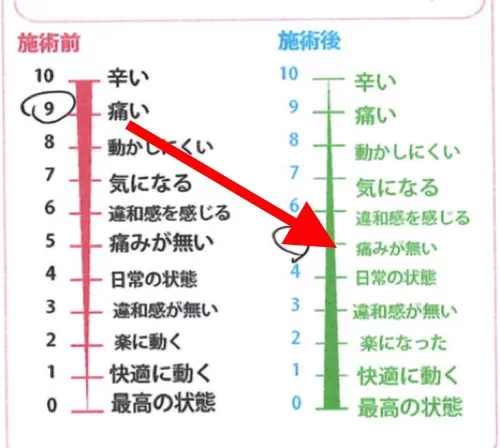

施術前後のアンケート

辛かった痛みが無くなりました^^

症状の進行具合や筋肉の硬直量などによっては

数回の施術が必要な場合が多いのですが

今回は1回の施術で痛みが消えました。